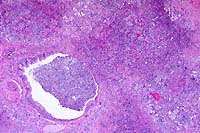

4x

obj.

- Case 22-1. Lung. Exudate fills an ulcerated bronchus

and extends into the surrounding parenchyma, obscuring normal

alveolar architecture.